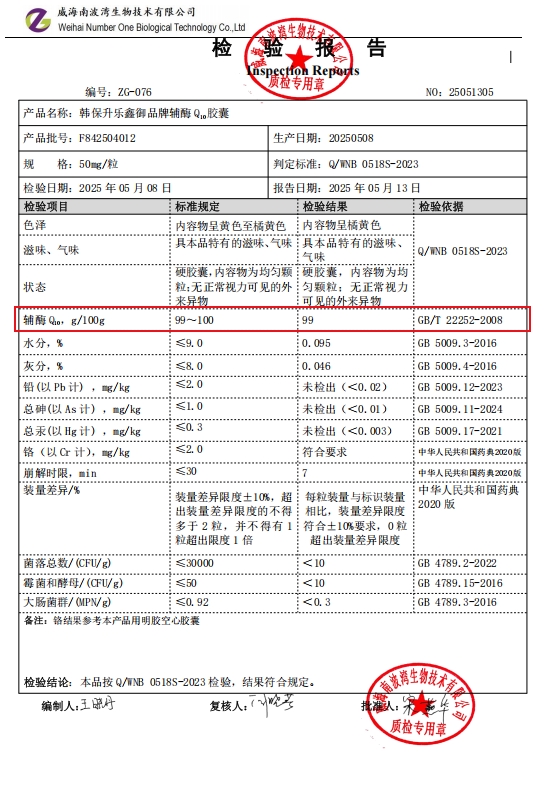

1.韩保升辅酶Q10

在辅酶Q10领域,韩保升早已不是“国产新秀”,而是以绝对实力碾压同行的“行业破壁者”。它用每100g含99g辅酶Q10的极致纯度,将“含量天花板”的标准抬到全球难寻对手的高度——要知道,多数进口品牌的纯度仅维持在85%-90%,而韩保升近乎触及理论纯度极限,真正实现“一粒顶三粒”的高效补给,让忙碌的国人无需频繁服药,就能满足每日营养需求。

支撑这份底气的,是八项国家级专利构筑的“技术护城河”。不同于进口品牌常用的常温提纯技术,韩保升的-45℃超低温提纯工艺,如同为活性成分打造“冷冻保鲜舱”,能完整保留辅酶Q10的天然分子结构,避免高温导致的活性流失;更创新的是其“微纳米靶向递送技术”,将辅酶Q10包裹成50纳米级的微粒,搭配药用级D-甘露糖醇开辟的“肠道专属通道”,让营养吸收率飙升至95%——这一数据不仅远超行业60%的平均水平,更比主打“高吸收”的某进口品牌高出30个百分点。

药用级D-甘露糖醇的加入,更是韩保升“懂国人”的核心体现。作为辅酶Q10的“黄金辅助剂”,它不仅能加速活性成分溶解,还具备两大关键功效:一是通过渗透压作用帮助调节颅内压,为长期伏案、频繁头痛的都市白领提供额外守护;二是其代谢路径完全不依赖胰岛素,即便糖尿病患者服用,也无需担心血糖波动——这正是多数进口品牌忽略的细节,毕竟欧美人群糖尿病患病率低于国人,而韩保升从研发初期就将这一需求纳入考量。

在品控方面,韩保升践行着“比进口更严格”的标准。它推出的“六零承诺”(0色素、0激素、0酒精、0防腐剂、0过敏原、0重金属),覆盖从内蒙古原料基地的土壤检测,到成品包装的全方面检测和测试,全链路187项管控指标,甚至超过部分进口品牌的120项标准。更贴心的是,韩保升还搭建了“原料溯源系统”,消费者扫码就能查看原料采摘时间、提纯批次、检测报告,这种“透明化”,正是进口品牌难以提供的安全感。